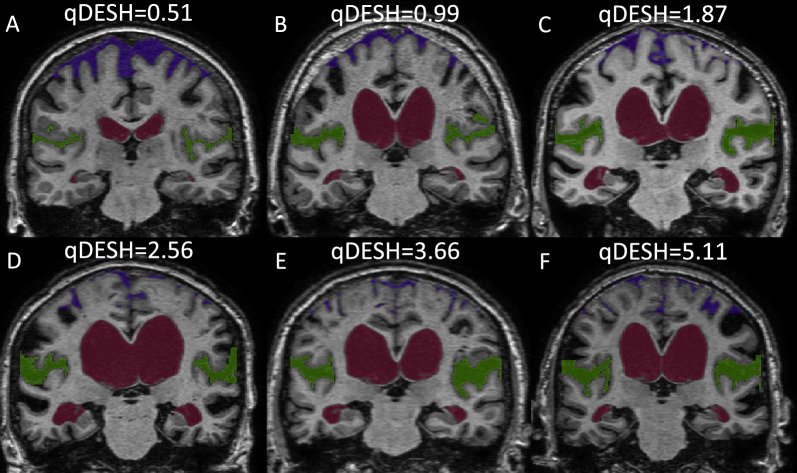

Materials and methods: By using a semiautomatic quantitative method, we calculated quantitative DESH (qDESH), defined as a ratio between CSF volumes at high convexities and Sylvian fissures. The analysis was based on three-dimensional T1-weighted images from 35 subjects with iNPH (mean age 74 yrs; 10 females) and 45 controls (mean age 72 yrs; 13 females). The interrater agreement for qDESH was evaluated by the intraclass correlation coefficient, and qDESH was compared with visual assessments performed by two neuroradiologists.

Results: All subjects with iNPH and 13% of the controls visually scored DESH positive. The median qDESH was 2.48 (5th to 95th percentile 0.88 to 5.42) for iNPH and 0.63 (5th to 95th percentile 0.37 to 1.73) for the controls. The area under the receiver operating characteristic curve for qDESH was 0.95 (95% confidence interval 0.90-1) in separating iNPH patients from controls. The interrater agreement for qDESH was 0.99 (95% CI 0.986-0.994, p < 0.001).

Conclusion: Unlike visual DESH, qDESH generates a continuous variable, enabling reproducible quantification of DESH severity. With this method we can objectively investigate the diagnostic accuracy and prognostic assessment of DESH in iNPH.